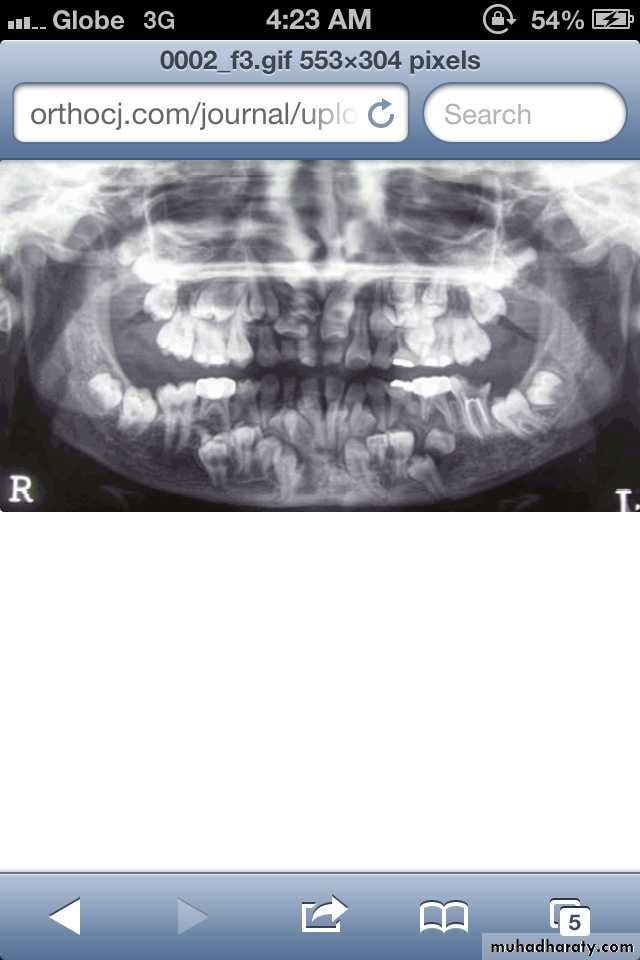

Hypodontia

Oligodontia

Anadontia

Developmental absence of all maxillary premolars and both mandibular second premolars. Note the retention of the maxillary primary canine as a result of the posterior position of the maxillary permanent canine.

CAUSES: may be the result of numerous independent pathologic mechanisms that can affect the orderly formation of the dental lamina (e.g.,orofaciodigital syndrome), failure of a tooth germ to develop at the optimal time, lack of necessary space imposed by a malformed jaw, and a genetically determined disproportion between tooth mass and jaw size.